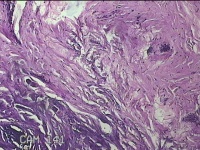

右颈部皮肤肿物

性别

女

年龄

29岁

临床诊断

纤维瘤

一般病史

右颈部皮肤起肿物10年左右。

标本名称

大体所见

灰白暗红色肿物0.3x0.2x0.1cm一个,表面光滑。

图3